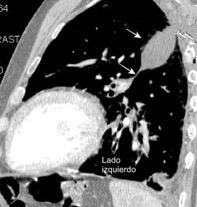

Marzo 2014: Perforación longitudinal distal secundaria a episodio de vómito (síndrome de Boerhaave). Derrame pleural izdo. que evoluciona a empiema.

Wang C-T et al. Tension hydropneumothorax in a Boerhaave syndrome patient: A case report . World J Emerg Med, 2021. Katabathina V et al. Nonvascular, nontraumatic mediastinal emergencies in adults:a comprehensive review of imaging findings. Radiographics. 2011.